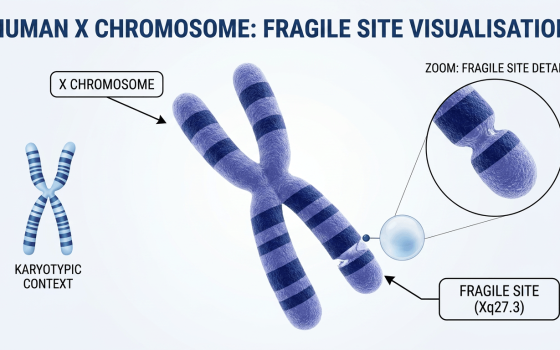

- Fragile X Syndrome